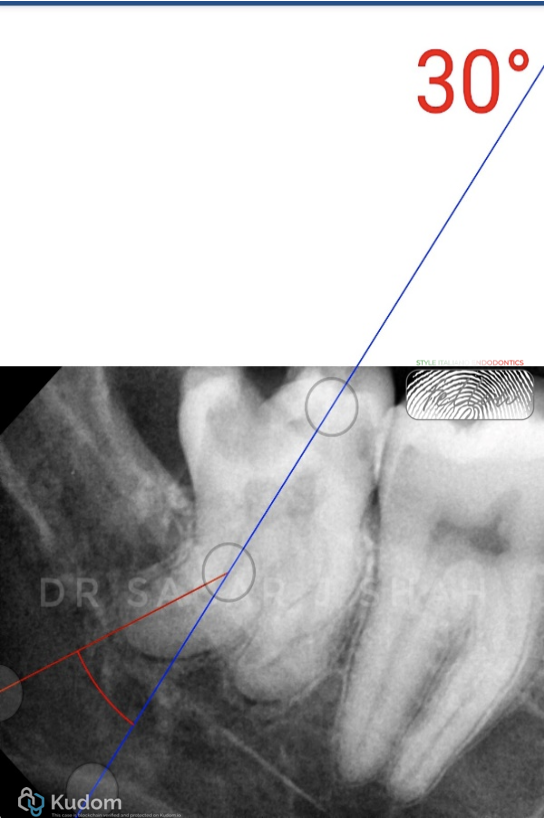

PREOPERATIVE ASSESSMENT:

Distal canal curvature- 30 degree

Close proximity to the mandibular canal.

Pulp calcification was seen with the distal root.

AAE DIFFICULTY ASSESSMENT- HIGH